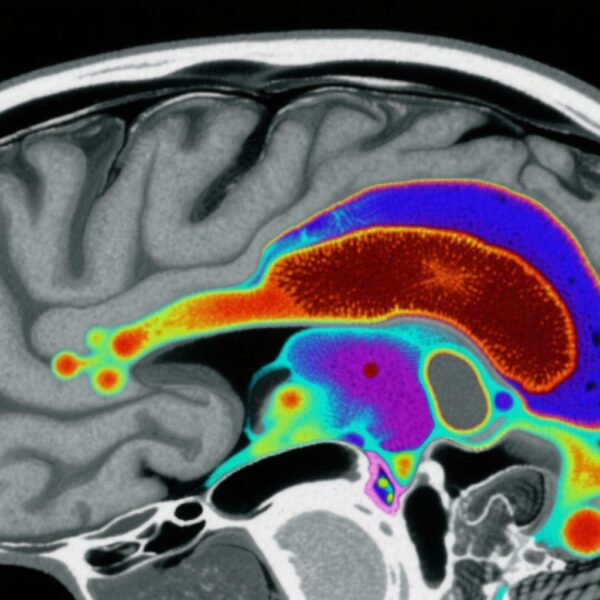

本研究利用了《精神和物质使用障碍患病率研究》的数据,该研究是一个具有全国代表性的非老年人美国成年人样本(N=4,764)。参与者接受了由临床医生管理的《DSM-5结构化临床访谈》(SCID-5)评估,以确定过去一年和终身SSDs(包括精神分裂症、分裂情感性障碍和短暂性精神分裂症)的患病率,以及识别阳性精神病症状。

研究显示SSD患病率存在显著的种族差异。非西班牙裔黑人的患病率为4.1%,显著高于非西班牙裔白人的1.2%。调整年龄和性别后,黑人参与者的SSD患病率是3.49倍(95% CI: 1.37–8.91),精神病症状的患病率是2.04倍(95% CI: 1.15–3.63)。非西班牙裔多族裔个体的SSD患病率为5.6%,调整后的OR为4.59(95% CI: 1.53–13.76)。

关键的是,在进一步调整社区SVM评分后,黑人种族与SSD之间的关联显著减弱(调整后的OR=2.49,95% CI: 0.63–9.90),并失去了统计学意义。类似地,精神病症状的差异也减少了(调整后的OR=1.69,95% CI: 0.83–3.44)。相比之下,对于非西班牙裔多族裔个体,即使调整了SVM评分,SSD的差异仍然显著(调整后的OR=3.95,95% CI: 1.30–12.00),尽管有所减弱。